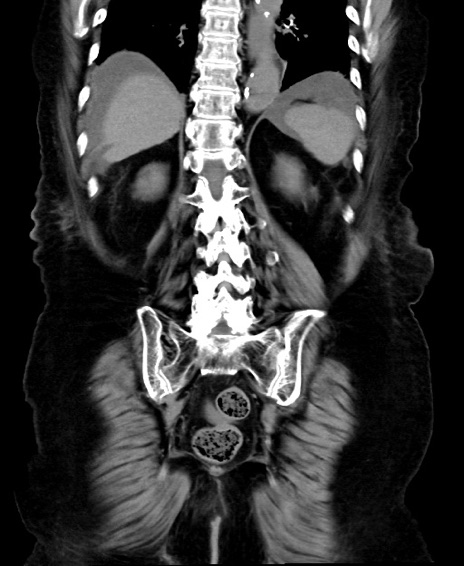

冠状断像

矢状断像